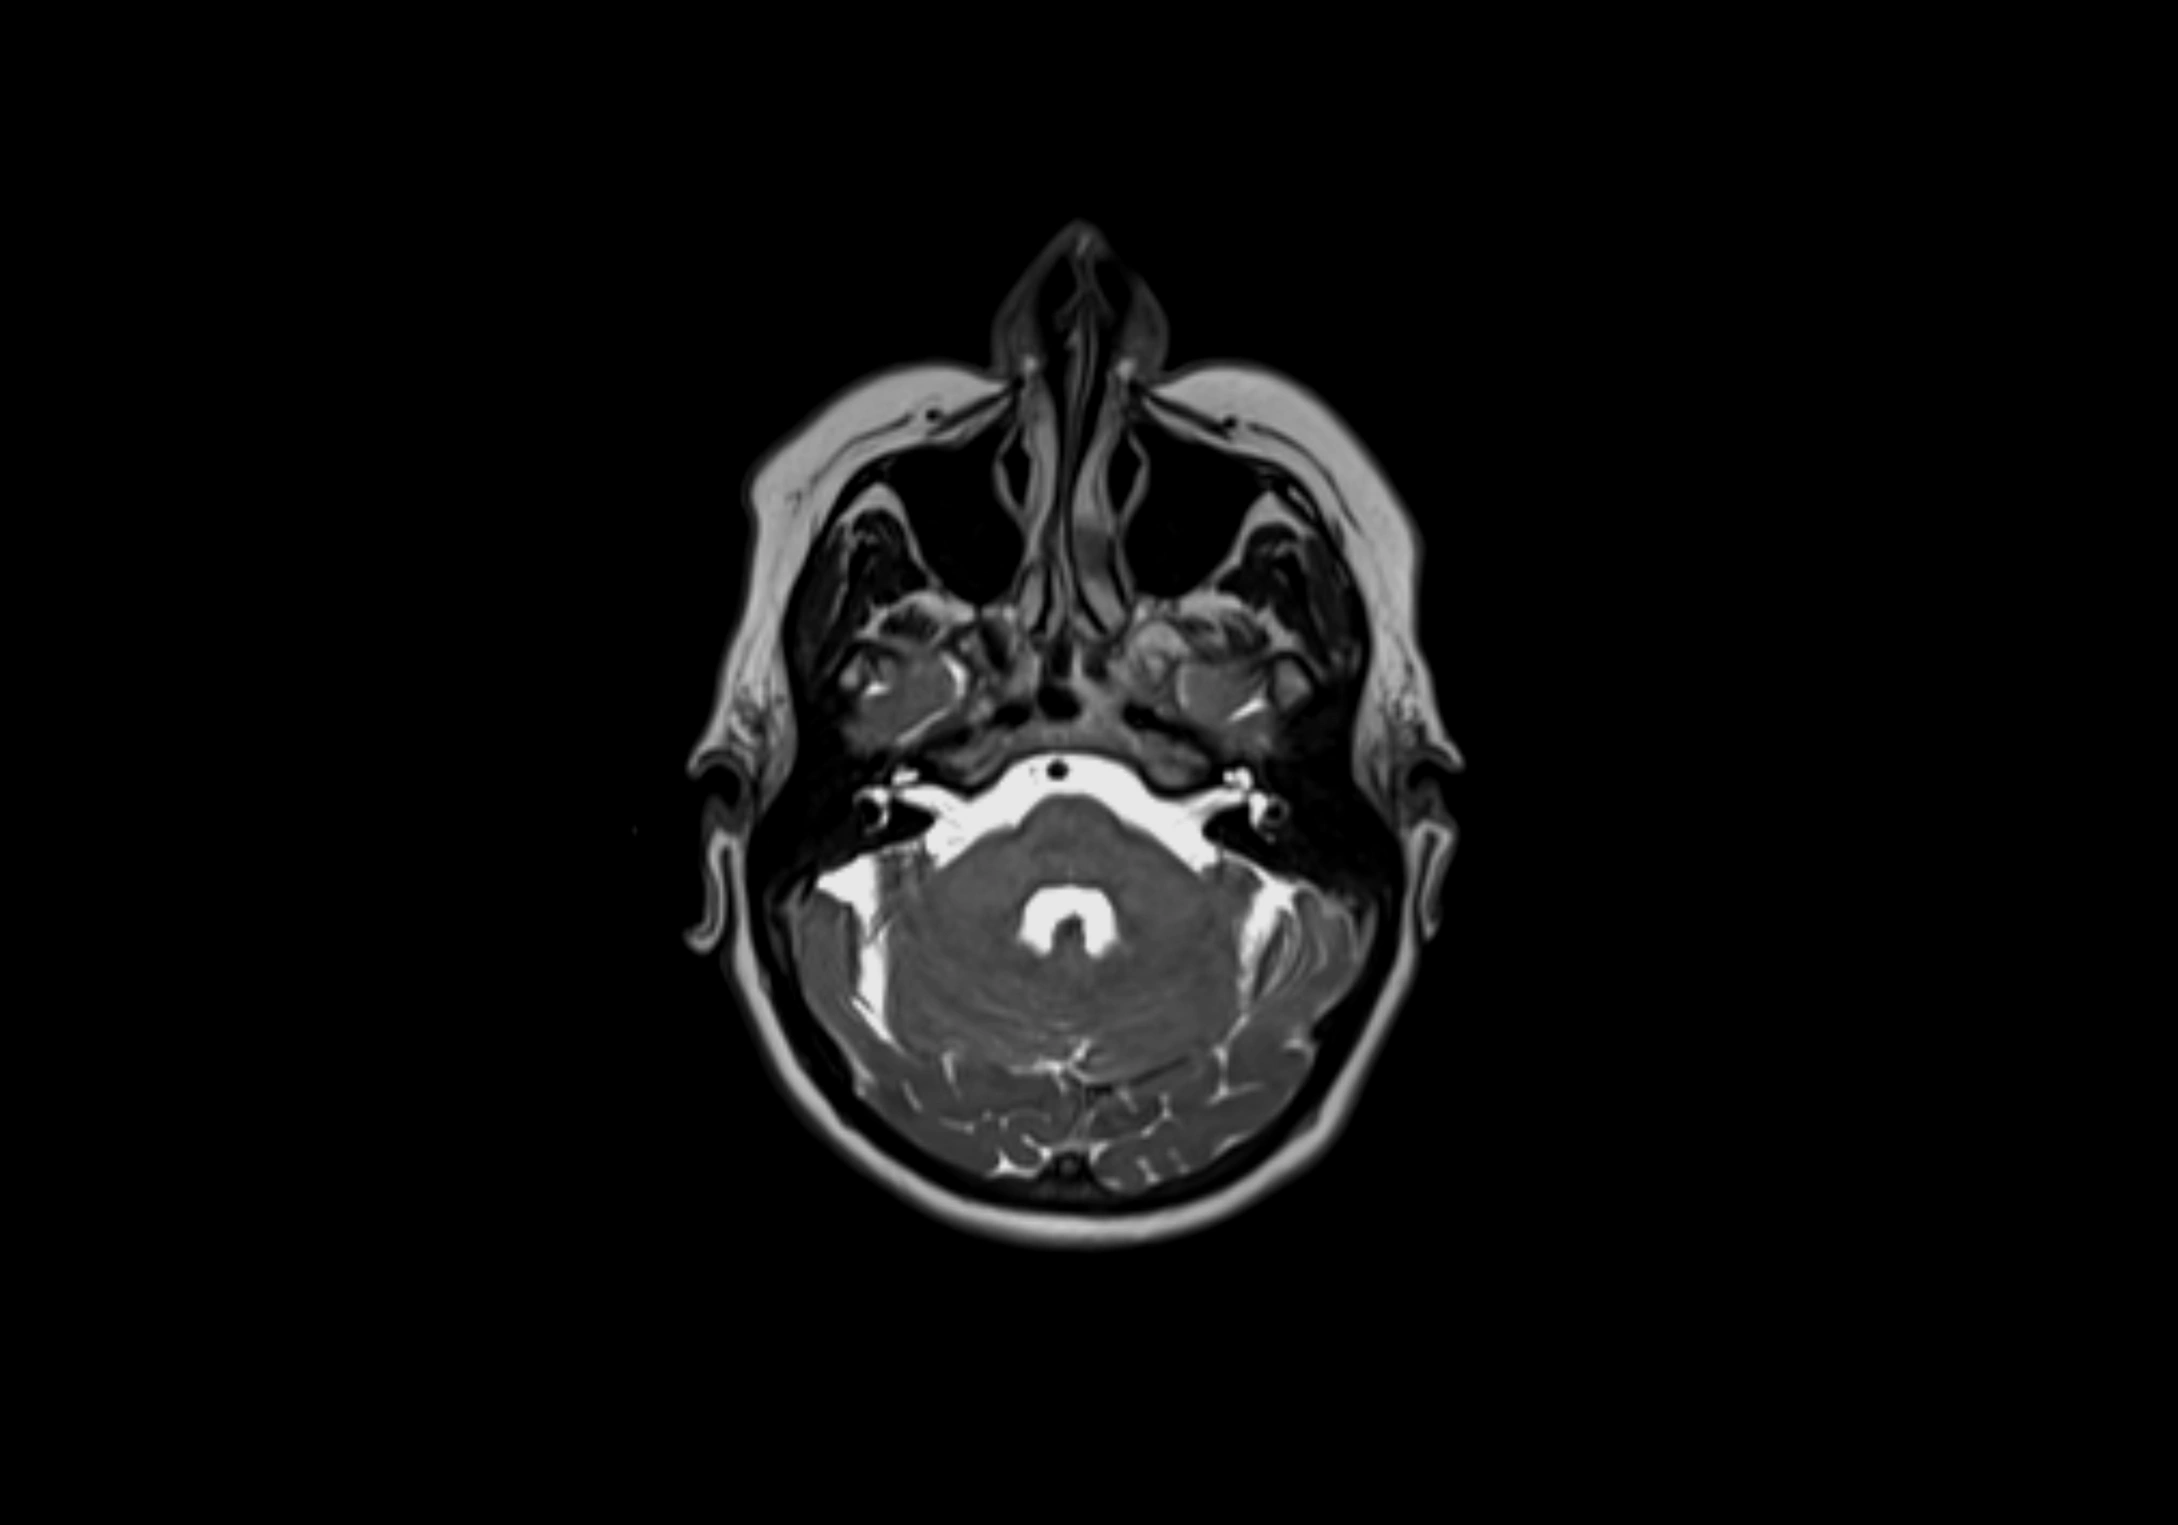

MRI Appearance

T1-weighted images:

• Normal accessory nodes appear as small, oval hypointense to intermediate signal structures within subcutaneous fat

• Surrounded by hyperintense fat, enhancing contrast for visualization

• Pathological nodes may appear enlarged or rounded, sometimes with cortical thickening

T2-weighted images:

• Nodes show intermediate signal, with surrounding fat bright

• Useful for detecting edema, inflammation, or infiltration

• Fatty hilum may appear slightly hyperintense relative to cortex